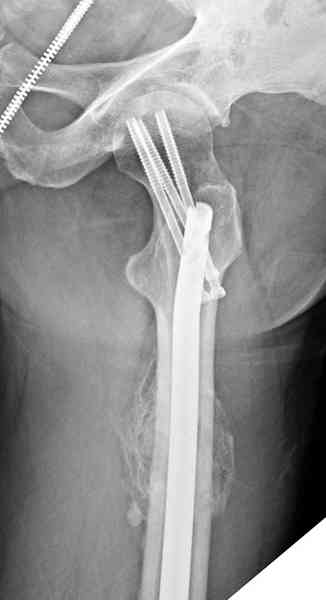

Здесь представлены снимки больного 65 лет, поступившего с диагнозом перелом

бедра после автоаварии.

В первый же день произведено антеградное штифтованием DePuy Trochanteric Nail.

На второй день (7) обнаружен пропущенный перелом,

сделаны Компьютерная Томограмма

и проведены шурурпы через и спереди штифта без удаления.

Послеоперационные снимки